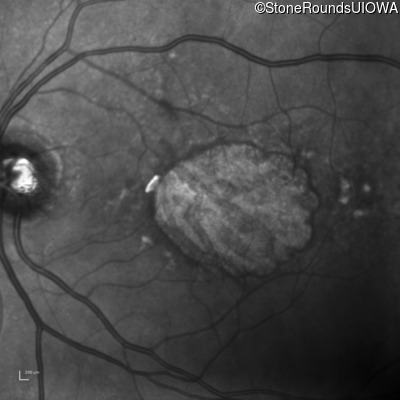

Infrared Fundus Photograph - Right - 20/125

Exemplar